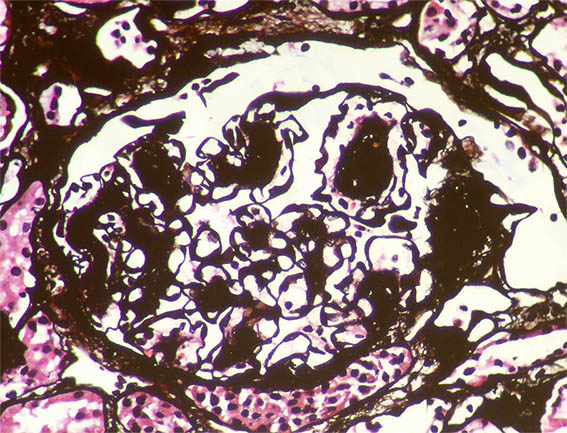

Figure 8. Methenamine-silver stain, X400.

Figure 10. Methenamine-silver stain, X400. Note the nodule on the upper right, surrounded by basement membrane (possibly microaneurysm with organizing thrombus).

Figure 12. Methenamine-silver stain, X1.000. The same nodule of figure 10; note "holes" in the basement membrane, on the left side.